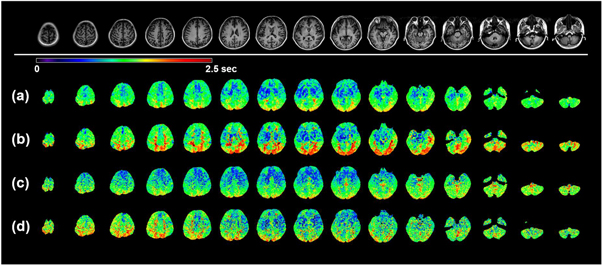

Standard image High-resolution imageThe ATT maps from the four datasets on the volunteer are shown in figure 4 for the same 15 slices as in figure 3. Similarly as what has been found in the CBF maps, not surprisingly, the regular spatial resolution ATT maps (figures 4(a) and (b)) present higher SNR than those with the high resolution (figures 4(c) and (d)). Notably however, this SNR loss is more significant compared to that of the CBF maps. The most remarkable difference in comparing these four sets of maps is that the ATT contrast among particular regions of the brain is much more pronounced in the GRASE acquisition with regular resolution and segmented kz (RR-S2, figure 4(b)). The contrast is interpreted in two perspectives. First if we look at tissues, WM generally exhibits longer ATT than GM. Second, occipital lobe and cerebellum in posterior circulation show longer ATT than frontal, parietal and temporal lobes in anterior circulation. This distinct contrast becomes obscure when utilizing conjoint kz GRASE acquisition (figure 4(a)). When high resolution acquisition is employed, SNR becomes an issue and this distinct contrast fades away (figure 4(d)). Further, if conjoint kz is used for the high resolution acquisition, an even more depressed contrast in obscure appearance is resulted (figure 4(c)).

Figure 4. ATT maps of multi-delay ASL using four GRASE acquisitions. The mapping results were acquired on the 29 y/o subject as a representation. 15 equidistant ATT maps out of total 32 slices are shown as a representation. Top row: T1 FSE FLAIR anatomical images for the same corresponding slices. With RR-S1(a), RR-S2(b), HR-S1(c), and HR-S2(d) acquisitions, variations of the ATT maps were resulted.

Standard image High-resolution imageTwo representative slices are selected from figures 3 and 4, and are displayed head-to-head in figure 5. In this enlarged comparison, the mapping characteristics mentioned above can be more clearly recognized. As for the CBF maps (figures 5(a) and (c)), high resolution kz segmented acquisition (HR-S2) offers the greatest GM/WM contrast in spite of the compromise of SNR. Nevertheless, RR-S2 shows reasonably good GM/WM contrast with the highest confidence in regard to SNR. The ATT maps for the four acquisitions are displayed in figures 5(b) and (d). Both regular and high resolution segmented kz acquisitions (RR-S2 and HR-S2) provide greater contrast in ATT maps compared to their counterparts using conjoint kz acquisitions (RR-S1 and HR-S1). However, diminished SNR is inherited for HR-S2. It is obvious that the occipital regions merely show a mosaic of moderately long and long ATT spots, indicative of insufficient SNR in the ATT estimation. An advantage of the regular resolution ATT mapping over the high resolution is that for GM abundant regions, such as the basal ganglia, clearer morphologies emerge (figure 5(d)), suggesting that the transit time contrast under the scanning parameters is superior. The morphological characteristics appear as well for the CBF mapping as presented in figures 5(a) and (c).

Figure 5. CBF and ATT maps of two exemplary slices magnified from figures 3 and 4. Left column: anatomical images of T1 FSE FLAIR for the two slices. Four GRASE acquisitions RR-S1, RR-S2, HR-S1, and HR-S2 are arranged from left to right for the CBF maps for the first slice (a) and second slice (c) and the ATT maps for the first slice (b) and second slice (d).

Standard image High-resolution imageThe CBF and ATT contrast differentiation among different acquisition approaches can be more clearly exhibited in the coronal and sagittal views. In figure 6, the coronal and sagittal central slices of the 3D brain of the volunteer for both CBF and ATT maps are shown. The enhanced GM/WM contrast in CBF maps and circulation contrast in ATT maps are evidently discerned in figures 6(b) and (d) using segmented kz acquisition in comparison to those using conjoint acquisition (figures 6(a) and (c)). Meanwhile, figures 6(b) and (d) display reduced degree of blurring along slice direction in respective comparison to figures 6(a) and (c), especially evident in the CBF mappings. In addition, similarly to what has been shown in axial slices in figures 4 and 5, in ATT maps of figure 6(b) the prolonged blood transit times in the occipital lobe and cerebellum in posterior circulation in contrast to frontal, parietal and temporal lobes in anterior circulation are clearly identified.

Figure 6. CBF and ATT maps in coronal and sagittal views using four GRASE acquisitions. The mapping results were acquired on the 29 y/o subject as a representation. Left two and right two columns are CBF maps and ATT maps, respectively. The results by four GRASE acquisitions RR-S1, RR-S2, HR-S1, and HR-S2 are respectively shown in (a), (b), (c), and (d).

Similarly to the CBF characteristics, RR-S2 (figure 4(b)) and HR-S2 (figure 4(d)) yield greater tissue contrast in respective comparison to RR-S1 (figure 4(a)) and HR-S1 (figure 4(c)). Amongst the four acquisitions, RR-S2 shows the greatest GM/WM tissue contrast (as summarized in table 2 and figure 7) and well depicts the contrast between cerebral lobes under different pathways of anterior and posterior circulations (highlighted prolonged arrival times in occipital lobe and cerebellum as in figures 4–6). RR-S1, HR-S1, and HR-S2 are likely to provide less reliable ATT quantification as they don't differentiate GM/WM tissues and circulations well enough. Specifically, with RR-S1, the average GM ATT is counterintuitively longer than that of WM, thus may not be considered appropriate for multi-delay ASL acquisition. It is a remarkable finding that scanning parameters of GRASE utilized in RR-S2 are more advantageous for ATT mapping.

Other than the tissue and circulation contrasts, the RR acquisition sets (figures 4(a) and (b)) generally show higher SNR than the HR ones (figures 4(c) and (d)). Similarly as in the CBF mappings, the regular resolution acquisition outperforms the high resolution as well for ATT estimation. The primary reason for this SNR difference is that RR possesses larger voxel size in the pristine ASL control/label images than HR does, such that this higher sensitivity passes on to the ATT determination from the perfusion curve. This finding is in line with the study by Dai et al (2012) who found that transit delay is an inherently low spatial resolution quantity.